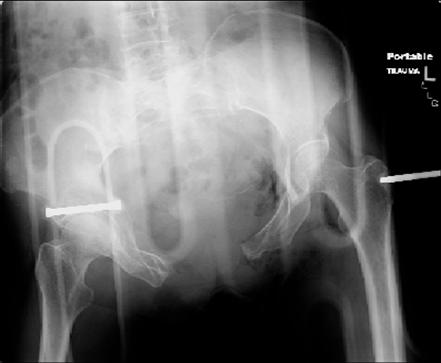

attached are images of a 70 year old female after peds versus car. her own car ran her over.

injuries are limited to the pelvis. left rami open and visible in a 10cm vertical laceration just lateral to left labia majora. wound is grossly clean. no vaginal and no urinary issues. CT scan shows widening of both SI joints anteriorly but I think this is vertically stable pattern.

pt treated that night with I/D and supra-acetabular frame to close the ring. consideration was given for SI screws bilateraly, but given time of night and other factors decision made not to proceed.

so the question is what next operatively if anything? concerns are infection, nonunion anteriorly and possible incompetence of the pelvic floor which may lead to prolapse issues. right rami are comminuted and plating may entail ilioinguinal approach to extend plate laterally to right iliac wing. retrograde screw up right rami is an option but I am not convinced it will add much. adding SI screws very doable, but major concern is restoring anterior ring. so far wound is clean and closed over a drain, and I have no plans to open it back up and wash again.

maintaining pelvic alignment in ex-fix in 70 yo female for any length of time may be challenging.

any thoughts? would anyone plate the pubic symphysis to close the gap and leave the more lateral rami fractures alone? the most recent pelvic case on this website involved pts with suprapubic catheters and antibiotic options including resorbable beads. I wonder how many people would plate and place antibiotic beads. thanks.

attached are several CT cuts. please let me know if you need more. the CT is pre-pelvic ex-fix placement.

Thank you.

Отправитель: Chip Routt 12 Июнь 2007, 04:53

I wouldn't plate the front.

But I would add screws posteriorly.